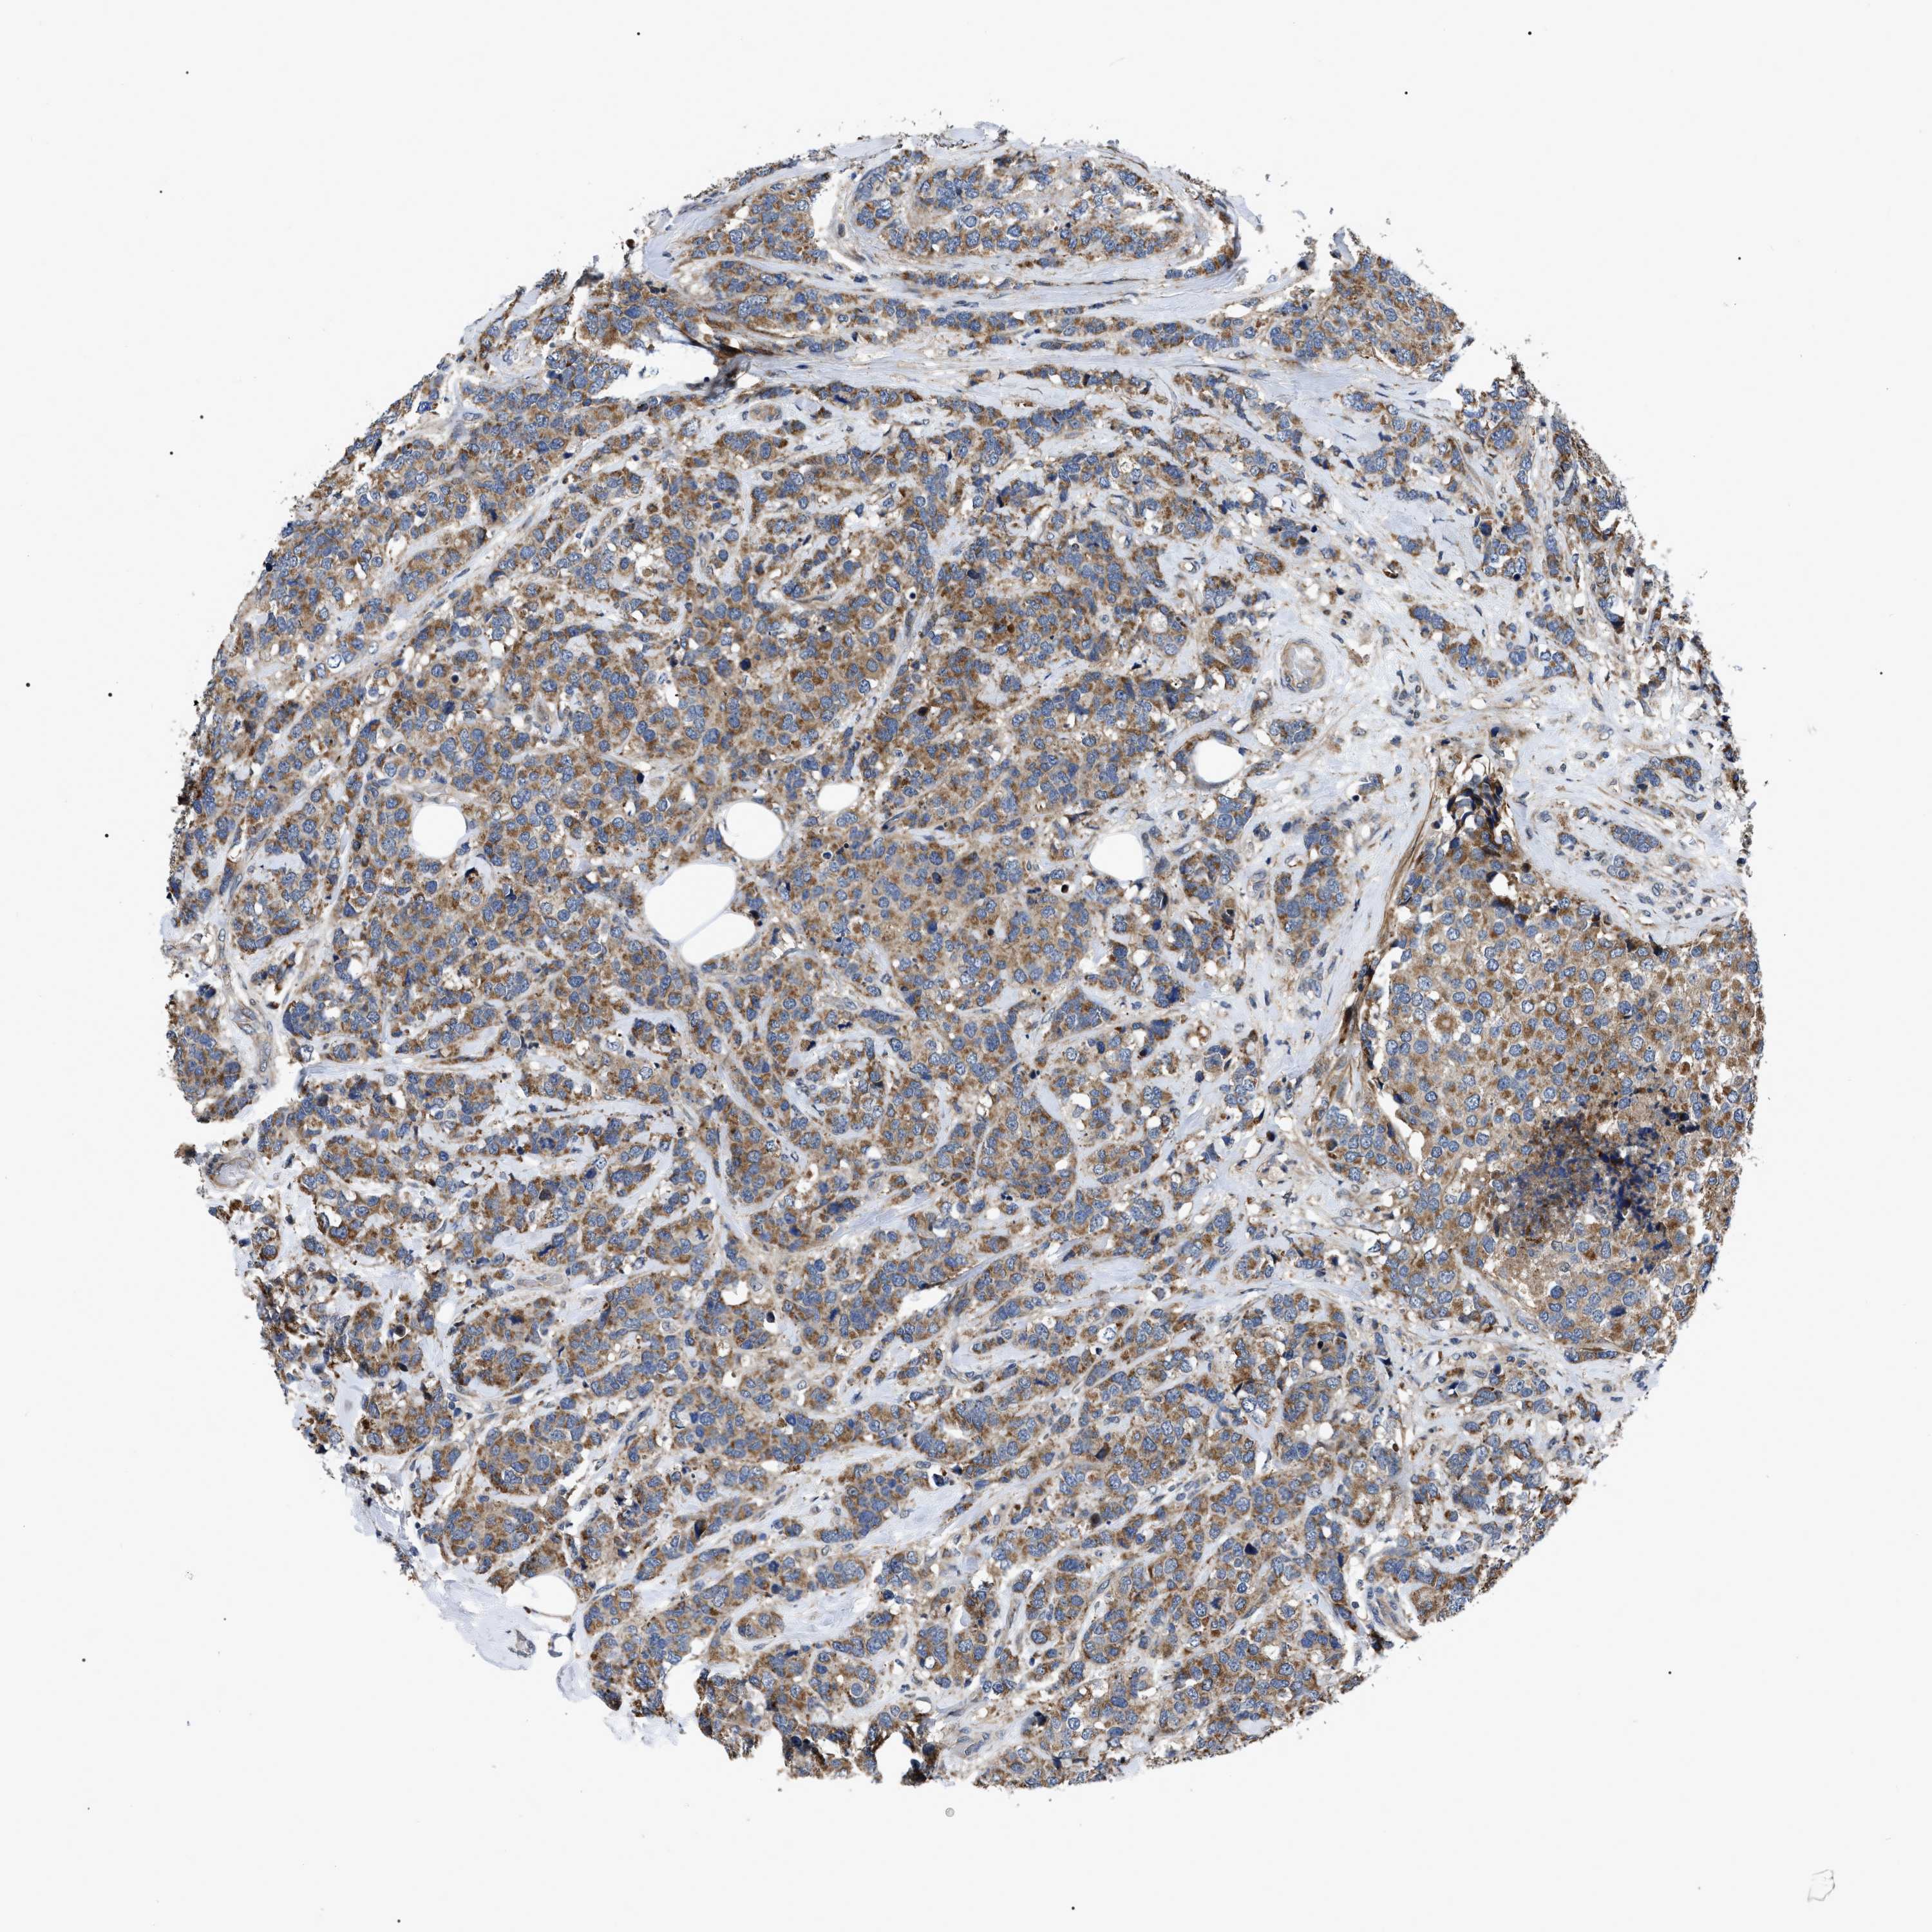

CANCER BREAST CANCER Show tissue menu

BRCA TCGA BRCA VALIDATION PROTEIN EXPRESSION